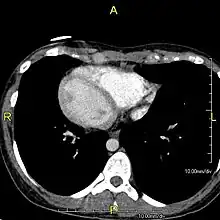

The condition affects all major structures within the thorax and abdomen. Generally, the organs are simply transposed through the sagittal plane. The heart is located on the right side of the thorax, the stomach and spleen on the right side of the abdomen and the liver and gall bladder on the left side. The heart's normal right atrium occurs on the left, and the left atrium is on the right. The lung anatomy is reversed and the left lung has three lobes while the right lung has two lobes. The intestines and other internal structures are also reversed from the normal, and the blood vessels, nerves, and lymphatics are also transposed.

If the heart is swapped to the right side of the thorax, it is known as "situs inversus with dextrocardia" or "situs inversus totalis". If the heart remains on the normal left side of the thorax, a much rarer condition (1 in 2,000,000 of the general population), it is known as "situs inversus with levocardia" or "situs inversus incompletus".

Diagnosis of situs inversus can be made using imaging techniques such as x-ray, ultrasound, CT scan, and magnetic resonance imaging (MRI).[7]